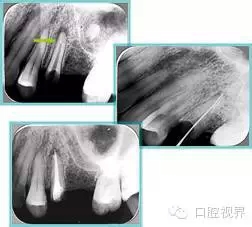

左圖和上圖為干髓治療后牙齒,齲齒疏通后進(jìn)行根管充填。

如圖為塑化加根充處理后牙齒 X 線片。

7.webp.jpg8.webp.jpg